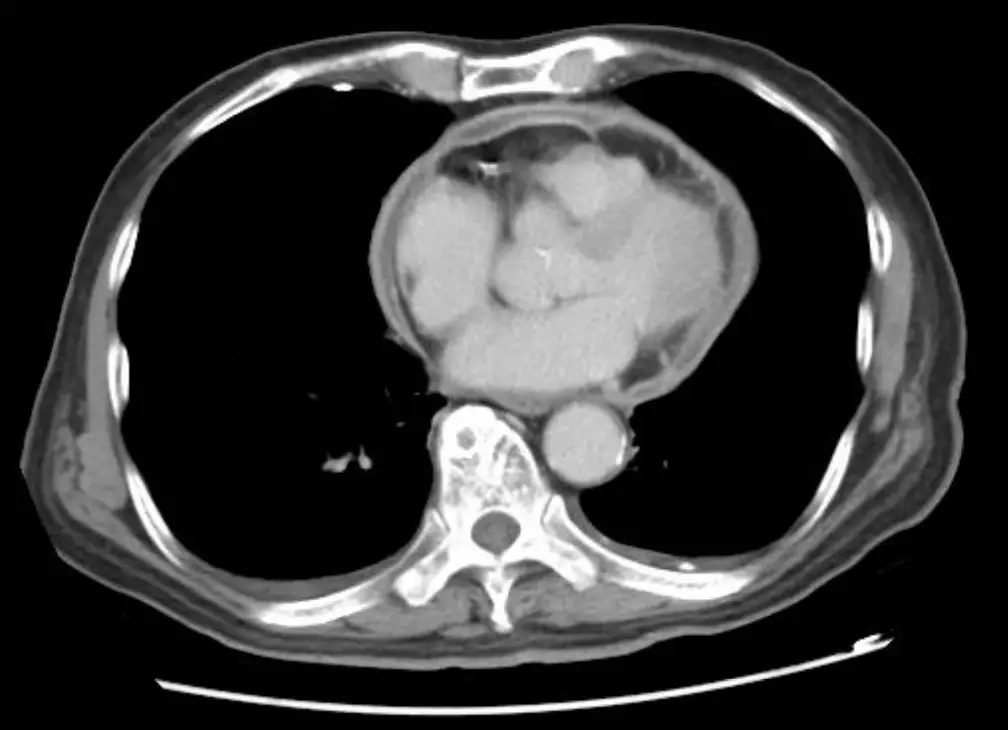

- 胸部電腦斷層(axial 與 coronal):可見心室壁弧形增厚,心包膜不增厚亦無鈣化;下腔靜脈與肝靜脈擴張,進一步支持系統靜脈鬱積。

整體影像組合指向 restrictive cardiomyopathy 而非 constrictive pericarditis或左心衰竭。